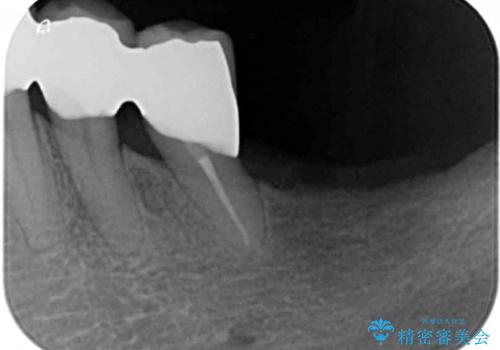

- 下の前歯(左下2)と奥歯の動揺がひどくなってきたことを主訴に来院された患者様です。

精査したところ、前歯の咬み合わせが反対になっていること、下の奥歯(下顎両側67)が4本欠損していることから動揺が生じていました。

入れ歯も抵抗があるとのことから、相談を重ね、今の状態では保存不可能な下の前歯(左下2)を抜去し、ブリッジや連結補綴により動揺を抑えることにしました。

下顎大臼歯が欠損したままで今ある歯に負担がかかりやすいことから、長期的予後は保証できないことをご理解頂いた上で治療を行いました。